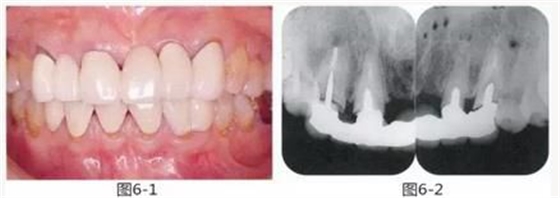

圖6-1

上頜前牙的牙頸部及齦下存在齲壞。

圖6-2 初診時(shí)的X光照片。齦下齲壞延伸到牙槽嵴頂,根管治療也不徹底。